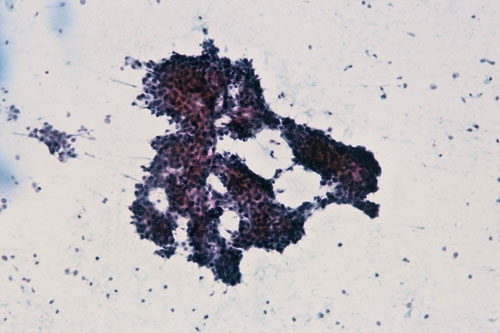

【症例2】内膜増殖症

(Pap染色×10)

(Pap染色×40)

採取部位:子宮体部

患者情報:58歳 女性

臨床所見:子宮体癌疑い

出現している細胞集塊は乳頭状あるいは不整突出(集塊辺縁より半島状に突出)が見られ、構造異型を示しています。

強拡大では核の飛び出しが無く、核の大小不同、クロマチンの異常や核小体肥大などといった細胞異型の所見は認められません。

類内膜腺癌では乳頭状、樹枝状、篩状集塊などの多数の構造異型を示す集塊に加え細胞異型も認められます。

本症例は細胞異型に乏しいため類内膜腺癌を否定できます。よって内膜増殖症を推定するのが適当です。